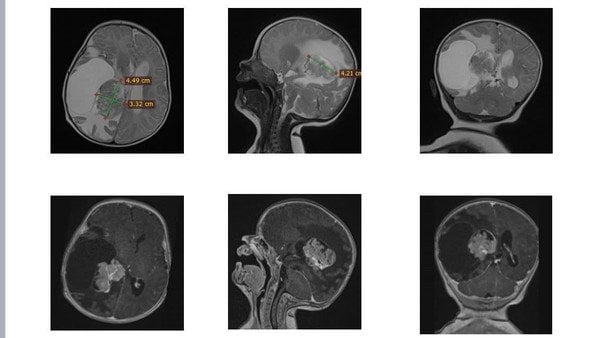

У Львові медики видалили пухлину у правому боковому шлуночку мозку двомісячної дитини.

У двомісячної Олівії з Рівного виявили пухлину у правому боковому шлуночку мозку. Дитина потребувала складного нейрохірургічного втручання.

Команда нейрохірургів успішно провела операцію: новоутвір вдалося повністю видалити, зберігши життя та здоров’я дитини.

«Утворення розташовувалося в зоні судинного сплетення з високим кровопостачанням, а отже, з високим ризиком значної крововтрати. До того ж пухлина була близько до ділянки, відповідальної за рухи. Тому операція вимагала максимальної точності та ретельної підготовки», — розповів керівник Клініки дитячої нейрохірургії Михайло Ловга.

Втручання тривало довше, ніж зазвичай: лікарям доводилося поетапно зупинятися, контролюючи крововтрату, та надзвичайно обережно видаляти утвір, щоб не пошкодити рухові зони мозку. Такі операції можливі лише за наявності інтраопераційного моніторингу та злагодженої роботи висококваліфікованої команди — нейрохірургів, нейрофізіологів, анестезіологів і операційних медсестер.